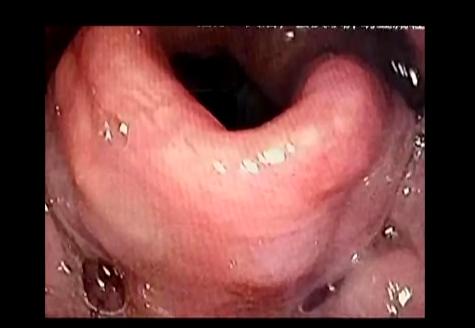

醫(yī)院緊急為張大爺進行了電子喉鏡檢查,發(fā)現(xiàn)張大爺?shù)暮聿砍霈F(xiàn)了非常嚴重的腫脹,如果再不及時治療,隨時會有窒息的風險。

西安大興醫(yī)院咽喉頭頸頜面外科主任 馬戈:“第二天病人情況明顯好轉(zhuǎn),復查喉鏡也發(fā)現(xiàn)大爺?shù)暮聿克[明顯減輕,治療三天后,張大爺便出院了!